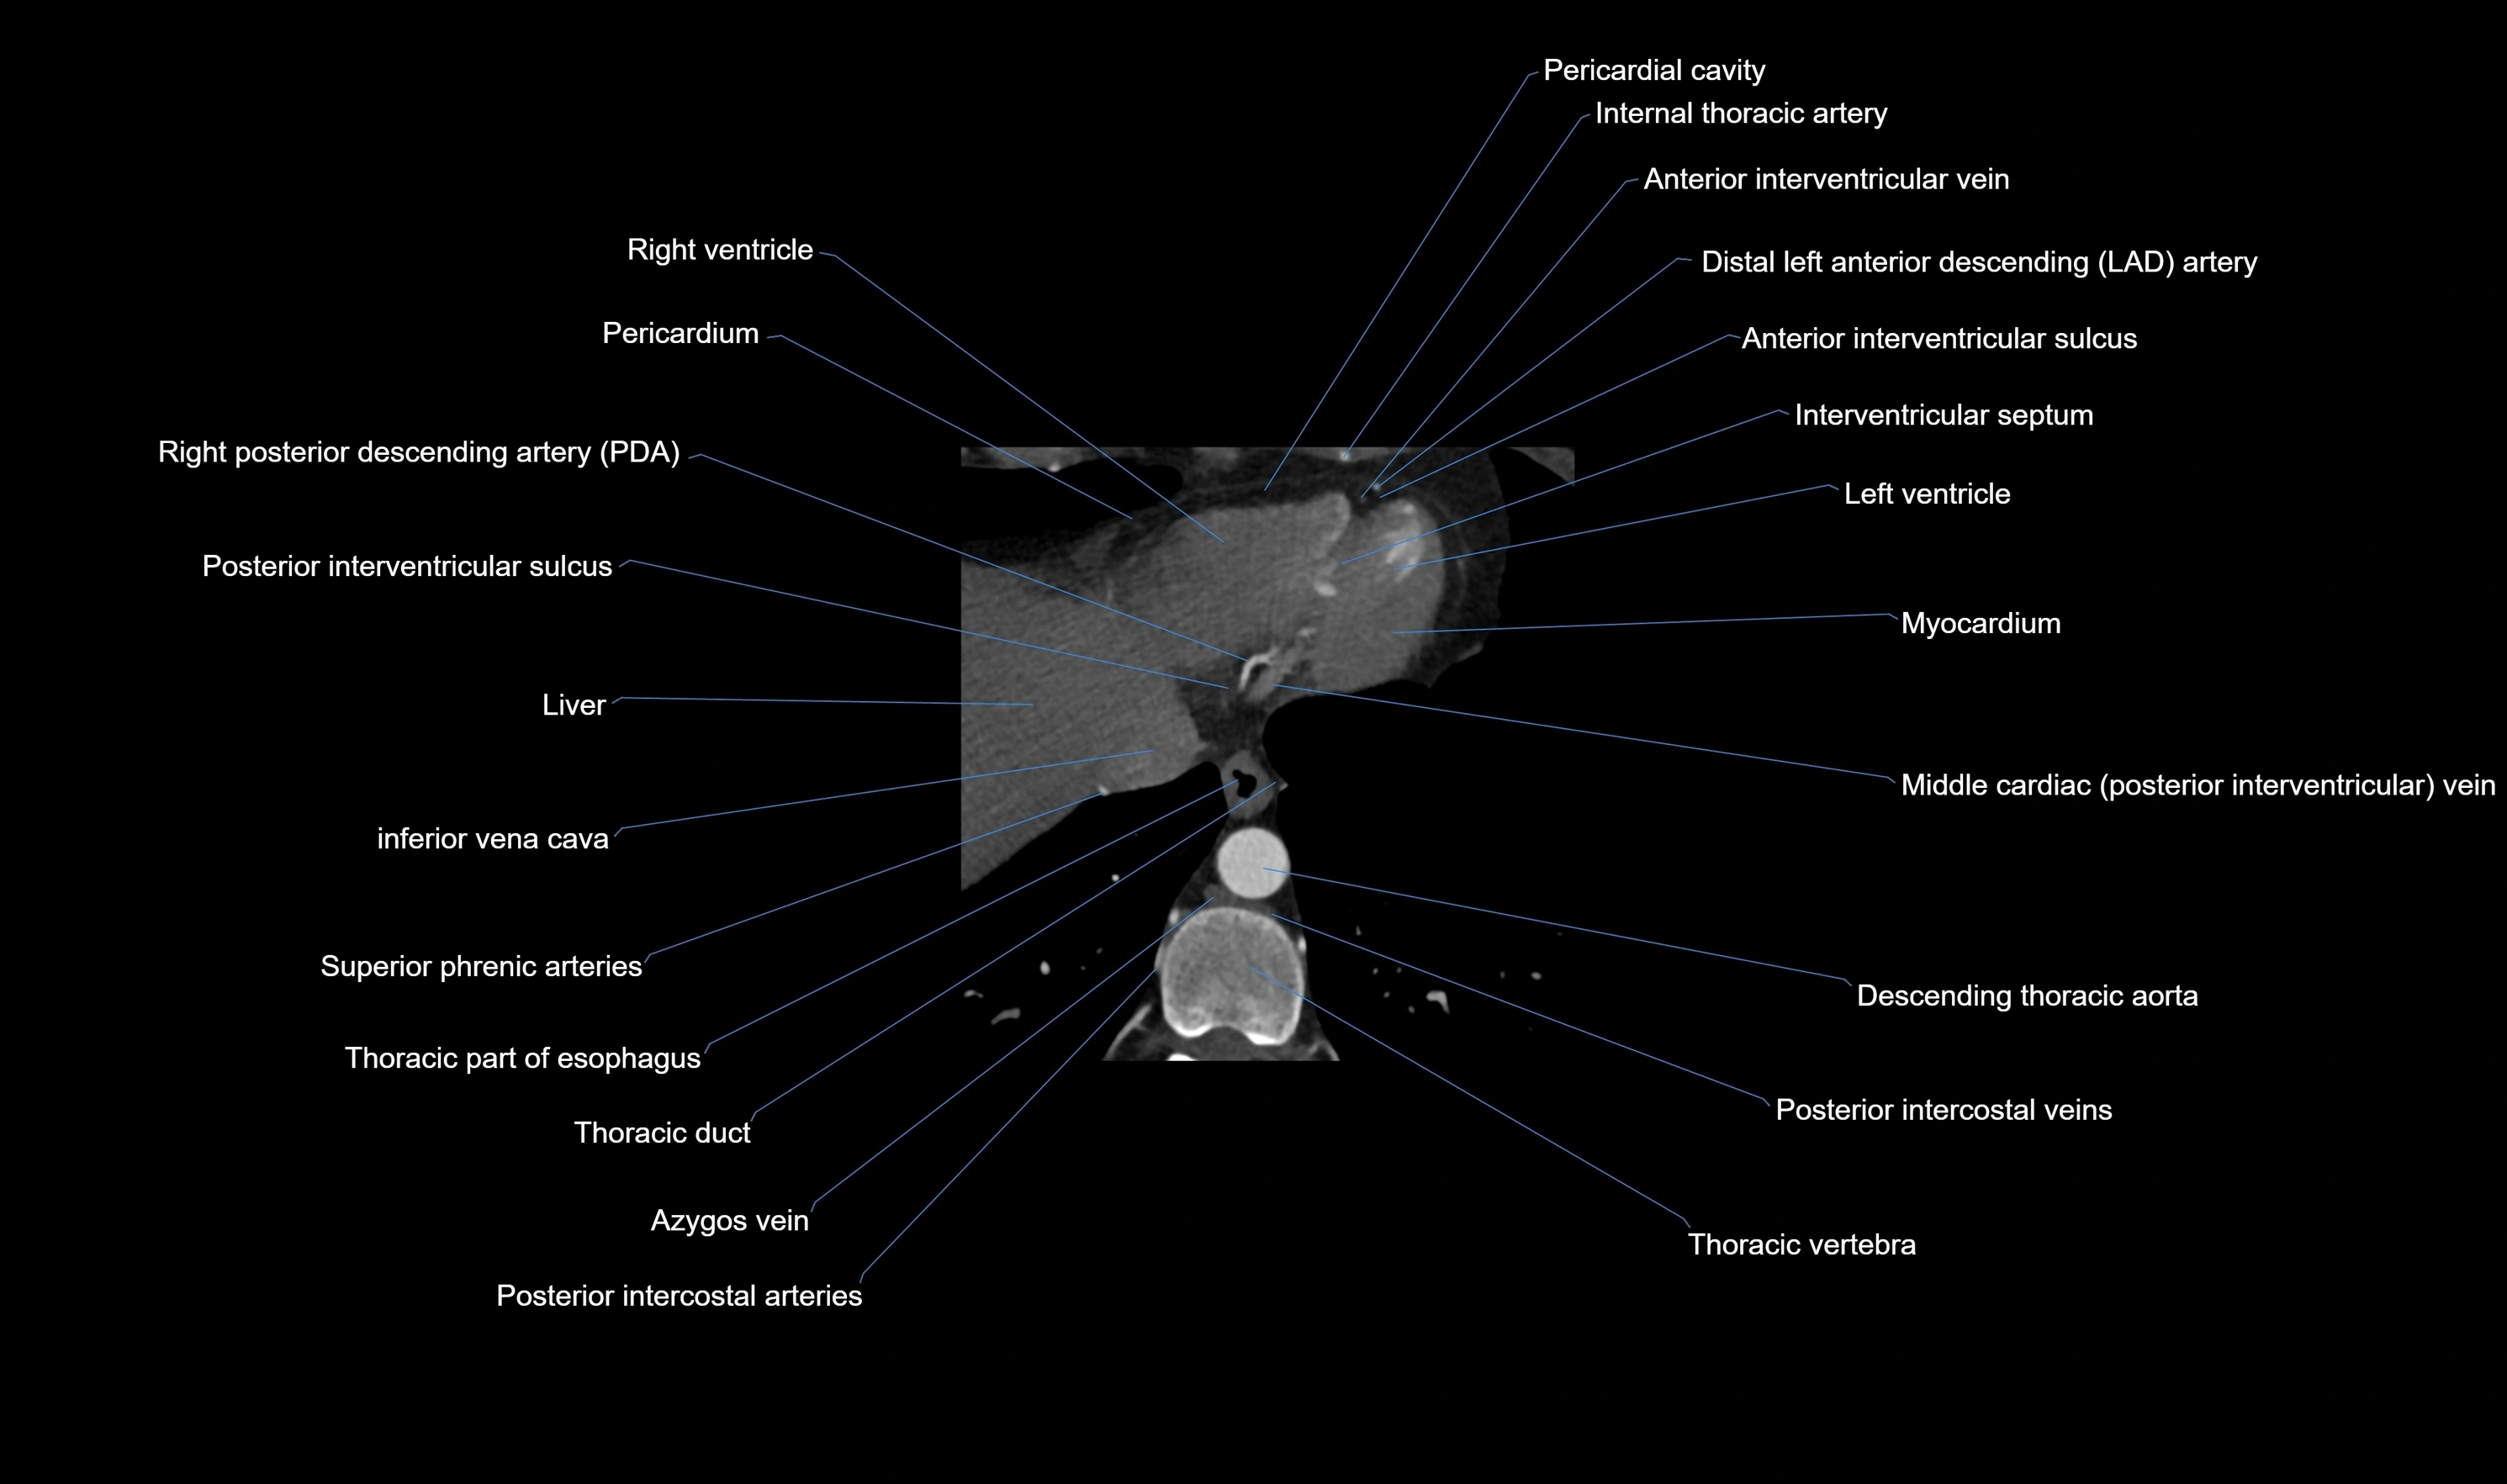

- Descending thoracic aorta

- Diaphragm

- Inferior vena cava

- Left ventricle

- Posterior intercostal arteries

- Posterior intercostal veins

- Posterior interventricular sulcus

- Right posterior descending coronary artery (Right PDA)

- Right ventricle

- Thoracic duct